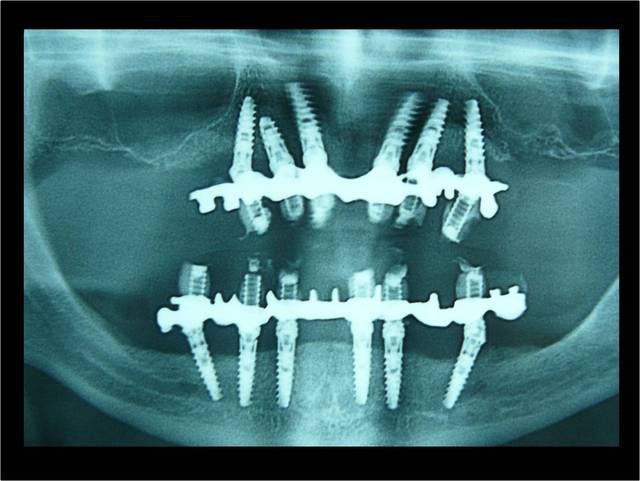

2 ANS après MCI Bimaxillaire en 1 intervantion

Image7 yplyva - Eugenol